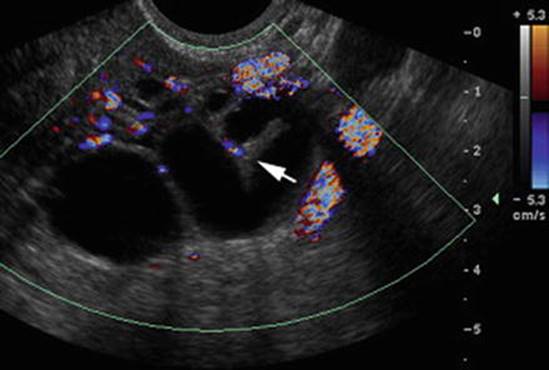

Fig. 4.10

Hydrosalpinx. Color Doppler coronal image shows a serpiginous anechoic tubular structure in the adnexa. Real-time imaging helps differentiate this tubular structure from complex adnexal cystic mass. Note the incomplete septation sign (arrow) (Reprinted from Chu et al. [66], with permission from Elsevier)